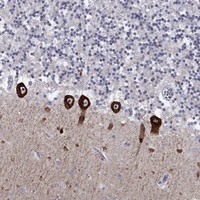

Immunohistochemical staining of human cerebellum shows strong cytoplasmic positivity in Purkinje cells.